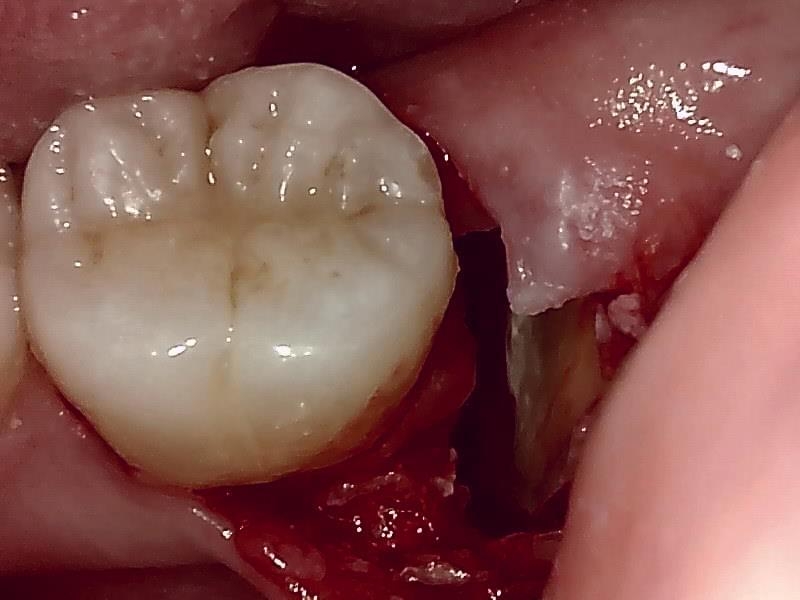

歯牙分割

歯冠除去

当院では、傷口は最小限に、骨は極力削らずに行います。

骨が歯を覆っているケース以外は骨を削ることはありません。

親知らずのみにアプローチし歯を分割し最小限の傷口で取り出します。